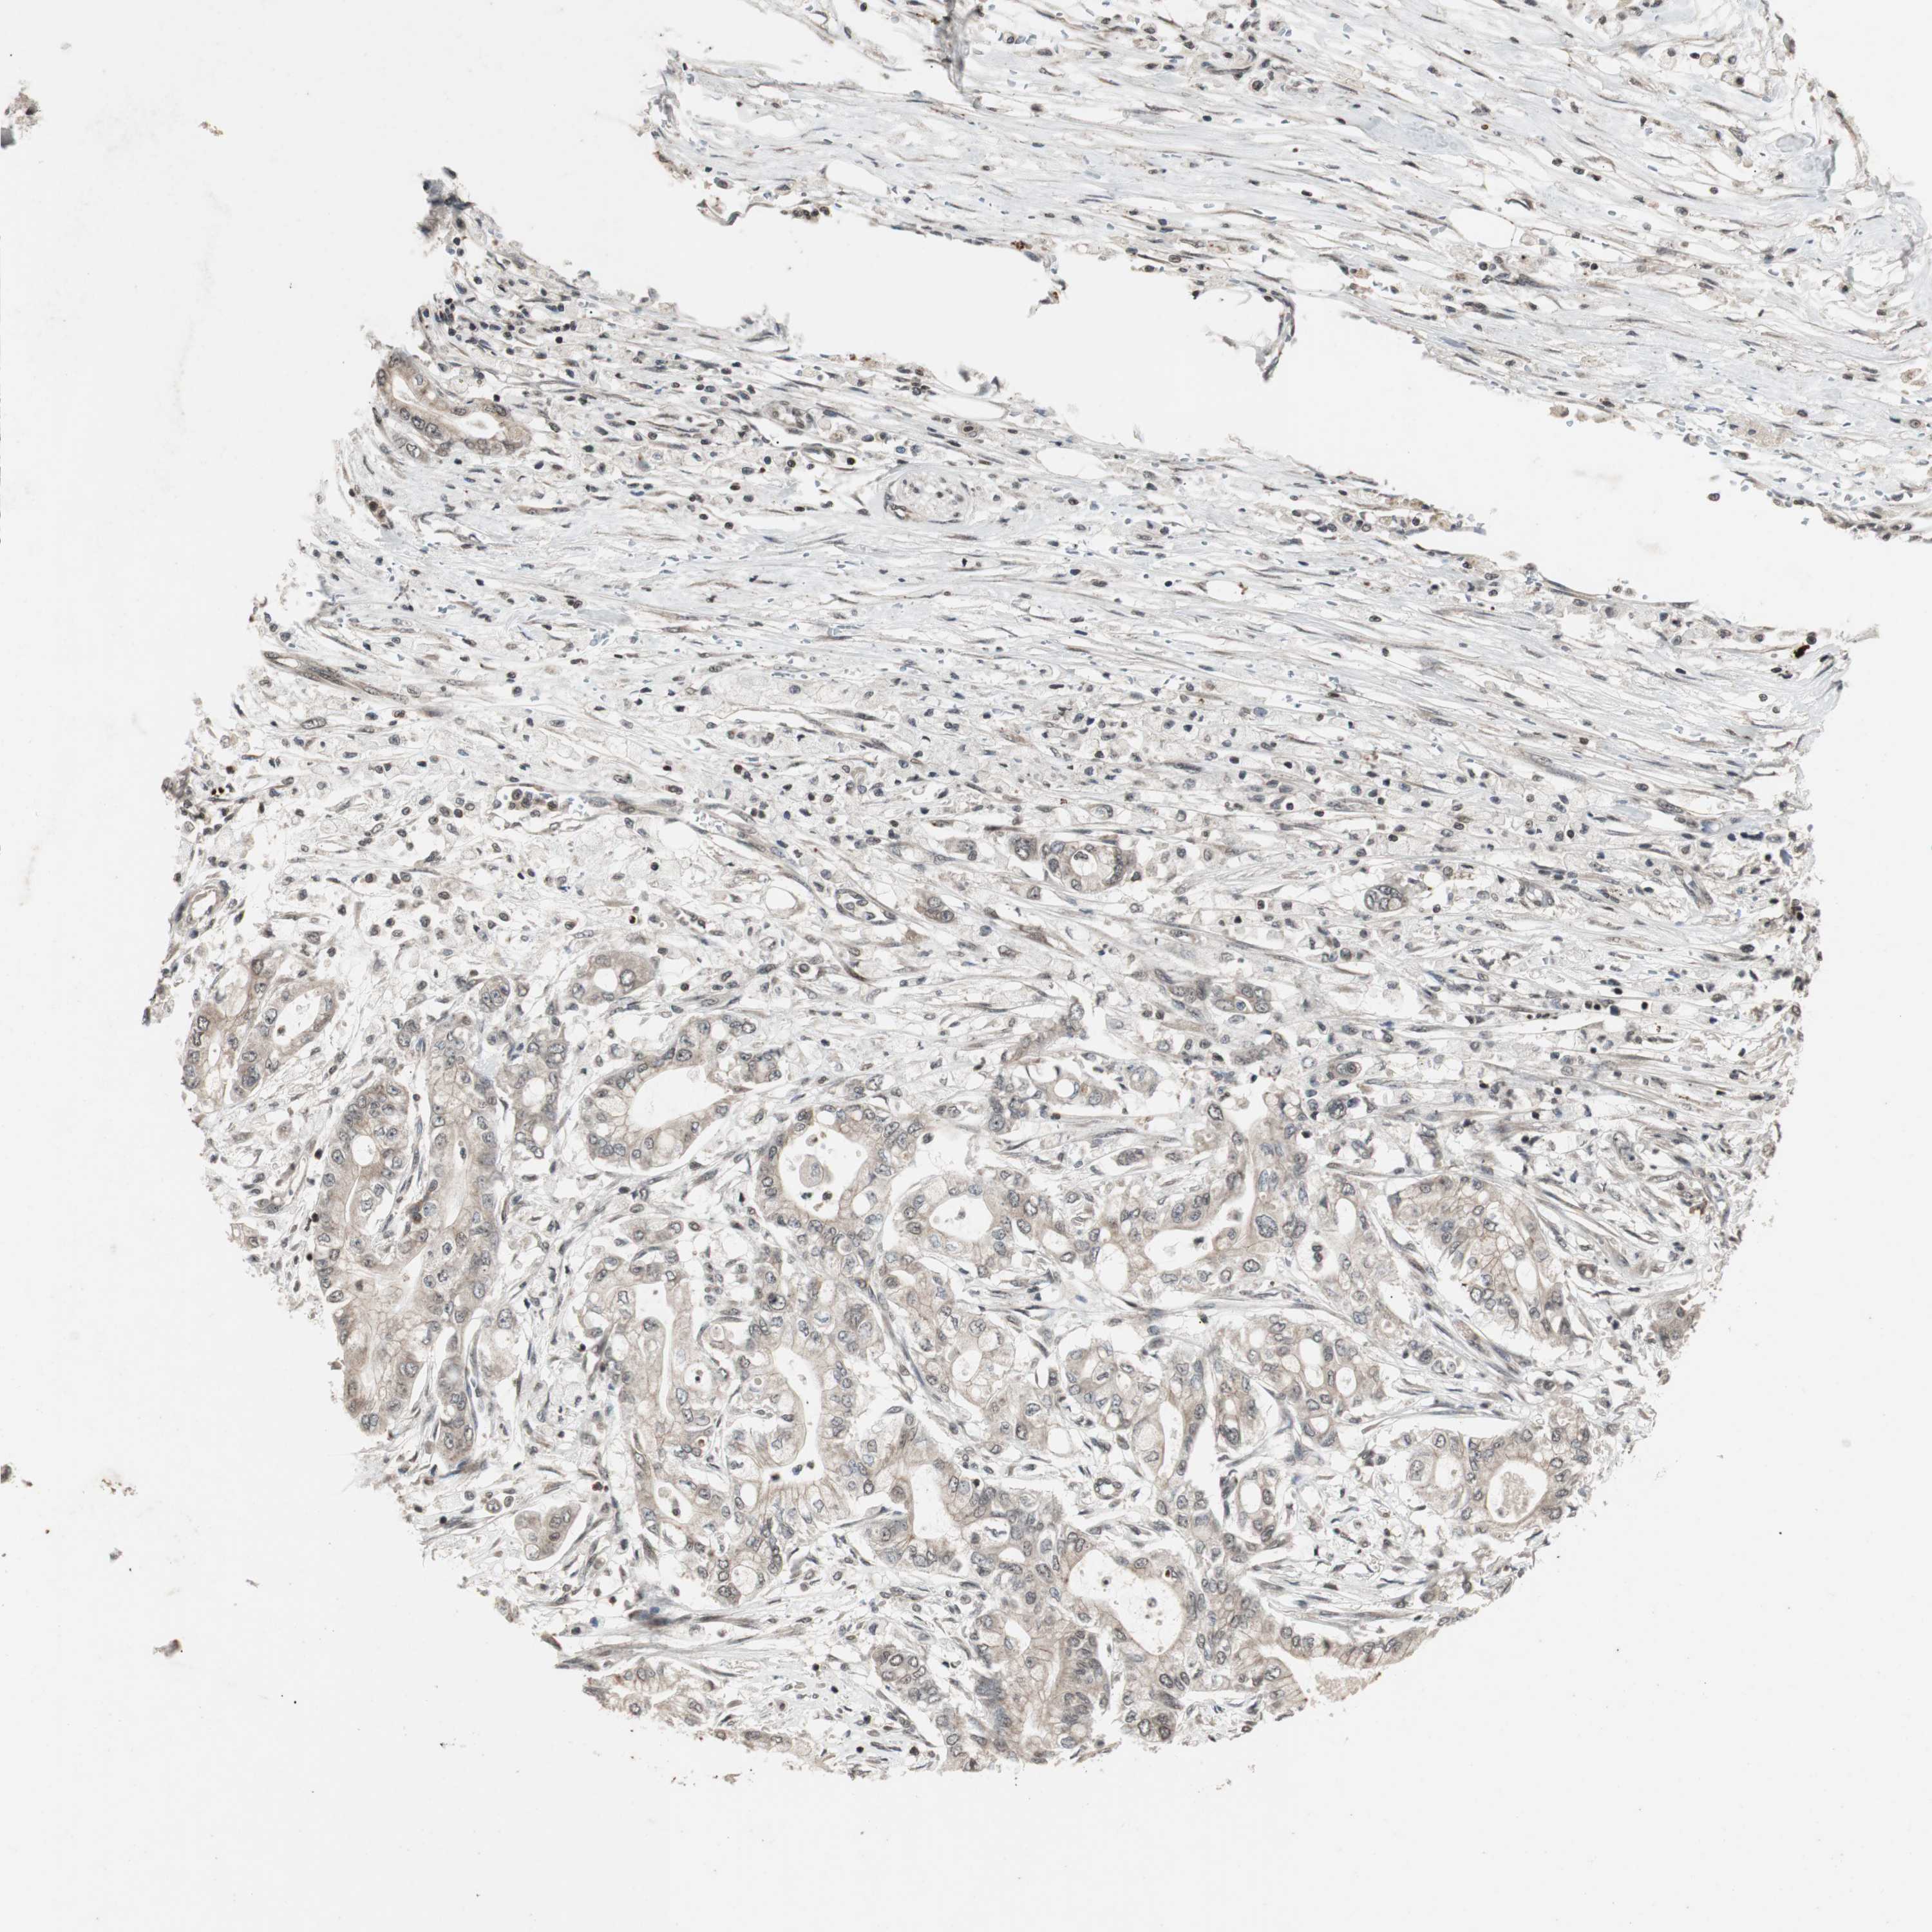

PANCREATIC CANCER - Protein expressioni

A mouse-over function shows sample information and annotation data. Click on an image to view it in a full screen mode. Samples can be filtered based on level of antibody staining by selecting one or several of the following categories: high, medium, low and not detected. The assay and annotation is described here.

Note that samples used for immunohistochemistry by the Human Protein Atlas do not correspond to samples in the TCGA dataset.

Antibody stainingi

Antibody staining in the annotated cell types in the current human tissue is reported as not detected, low, medium, or high, based on conventional immunohistochemistry profiling in selected tissues. This score is based on the combination of the staining intensity and fraction of stained cells.

Each image is clickable and will lead to virtual microscopy that enables deeper exploration of all samples and also displays staining intensity scores, fraction scores and subcellular localization as well as patient and tissue information for each sample.

Antibody HPA007072

Antibody HPA007151

Staining

High

Medium

Low

Not detected

Intensity

Strong

Moderate

Weak

Negative

Quantity

>75%

75%-25%

<25%

None

Location

Nuclear

Cytoplasmic/membranous

Cytoplasmic/membranous,nuclear

Adenocarcinoma, NOS

Adenocarcinoma, metastatic, NOS